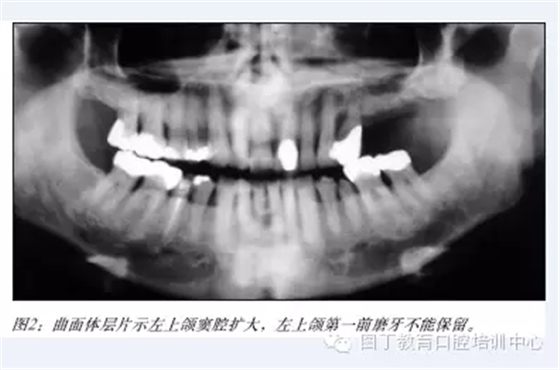

據(jù)筆者可獲得的有限的研究表明:術(shù)者經(jīng)過(guò)專業(yè)培訓(xùn),選擇適當(dāng)?shù)牟±?,上頜竇提升植骨術(shù)是一項(xiàng)成熟的種植外科技術(shù)(見(jiàn)圖2-6),種植體植入移植骨后的五年成功率達(dá)到95%以上。